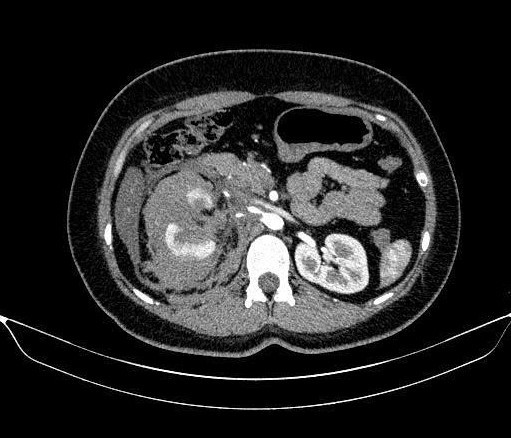

Kết quả cho thấy bệnh nhân bị vỡ thận phải độ IV theo phân loại AAST 2018 là mức độ tổn thương nặng, nguy cơ cao phải cắt thận nếu xử trí không kịp thời.

Hình ảnh chụp CT bụng của bệnh nhân. Ảnh: BVCC

Ca can thiệp do ThS.BSCKII Lê Hồng Kỳ, Trưởng khoa Chẩn đoán hình ảnh & Y học hạt nhân, trực tiếp thực hiện. Chụp động mạch thận phải ghi nhận tình trạng thoát thuốc từ các nhánh động mạch cực dưới. Ê kíp tiến hành can thiệp siêu chọn lọc bằng microcatheter, nút mạch bằng hỗn dịch Histoacryl – Lipiodol kết hợp Spongel.

Chụp kiểm tra sau can thiệp cho thấy các nhánh mạch tổn thương được tắc hoàn toàn, phần nhu mô thận còn lại được bảo tồn tốt. Thủ thuật diễn ra an toàn, không ghi nhận biến chứng trong và ngay sau can thiệp.